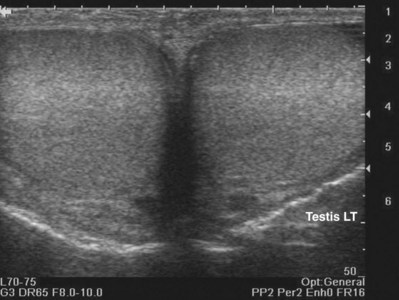

Figure 4–19 Fine internal echogenicity called “speckle” is caused by scattering of sound waves and the resultant pattern of interference. Note the resulting finely granular, homogenous echogenicity (arrows) of the testicular parenchyma.

By convention, structures imaged by ultrasonography should be oriented so that the superior aspect of the structure is to the left as the image is viewed and the inferior aspect of the structure to the right. With paired structures it is critically important to document right or left. It is useful to use equipment-generated icons to illustrate patient position and the orientation of insonation (Fig. 4–30).

Figure 4–30 In this sagittal image of the right testis, the superior pole of the testis (A) is to the left, the inferior pole of the testis (B) is to the right. The anterior aspect of the testis (C) is at the top of the image and the posterior aspect (D) at the bottom. Without the label, there would be no way to distinguish the right from the left testis.